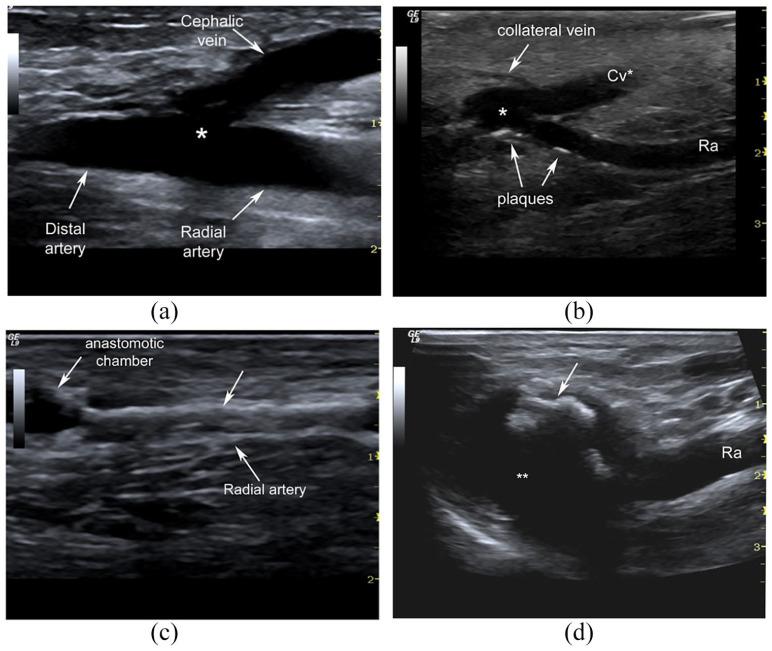

In the last years, the systematic use of ultrasound mapping of the upper limb vascular network before the arteriovenous fistula (AVF) implantation, access maturation, and clinical management of late complications is widespread and expanding. Therefore, a good knowledge of theoretical outlines, instrumentation, and operative settings is undoubtedly required for a thorough examination. In this review, the essential Doppler parameters, B-Mode setting, and Doppler applications are considered. Basic concepts on the Doppler shift equation, angle correction, settings on pulse repetition frequency, operative Doppler frequency, gain are reported to ensure adequate and correct sampling of blood flow velocity. A brief analysis of the Doppler inherent artefacts (as random noise, blooming, aliasing, and motion artefacts) and the adjustment setting to minimize or eliminate the confounding artefacts are also considered. Doppler aliasing occurs when the pulse repetition frequency is set too low. This artefact is particularly frequent in vascular access sampling due to the high velocities range registered in the fistula's different segments. Aliasing should be recognized because its correction is crucial to analyse the Doppler signals correctly. Recent advances in instrumentation are also considered about a potential purchase of a portable ultrasound machine or a top-of-line, high-end, or mid-range ultrasound system. Last, the pulse wave Doppler setting for vascular access B-Mode and Doppler assessment is summarized.

在过去的几年中,在动静脉瘘 (AVF) 植入、通路成熟和晚期并发症的临床管理之前,对上肢血管网络进行系统的超声映射的应用已经广泛普及并在不断扩展。因此,对彻底的检查无疑需要很好地了解理论概述、仪器和手术设置。在这篇综述中,考虑了基本的多普勒参数、B 模式设置和多普勒应用。报告了关于多普勒频移方程、角度校正、脉冲重复频率、手术多普勒频率、增益的基本概念,以确保对血流速度进行充分和正确的采样。还简要分析了多普勒固有伪像(如随机噪声、晕影、混叠和运动伪像)以及调整设置以最小化或消除干扰伪像的问题。当脉冲重复频率设置得太低时,会发生多普勒混叠。由于在瘘管的不同部位记录到的速度范围很高,因此在血管通路采样中这种伪像特别频繁。应识别混叠,因为正确分析多普勒信号至关重要。还考虑了仪器的最新进展,包括关于购买便携式超声机或高端、高端或中端超声系统的潜在选择。最后,总结了用于血管通路 B 模式和多普勒评估的脉冲波多普勒设置。